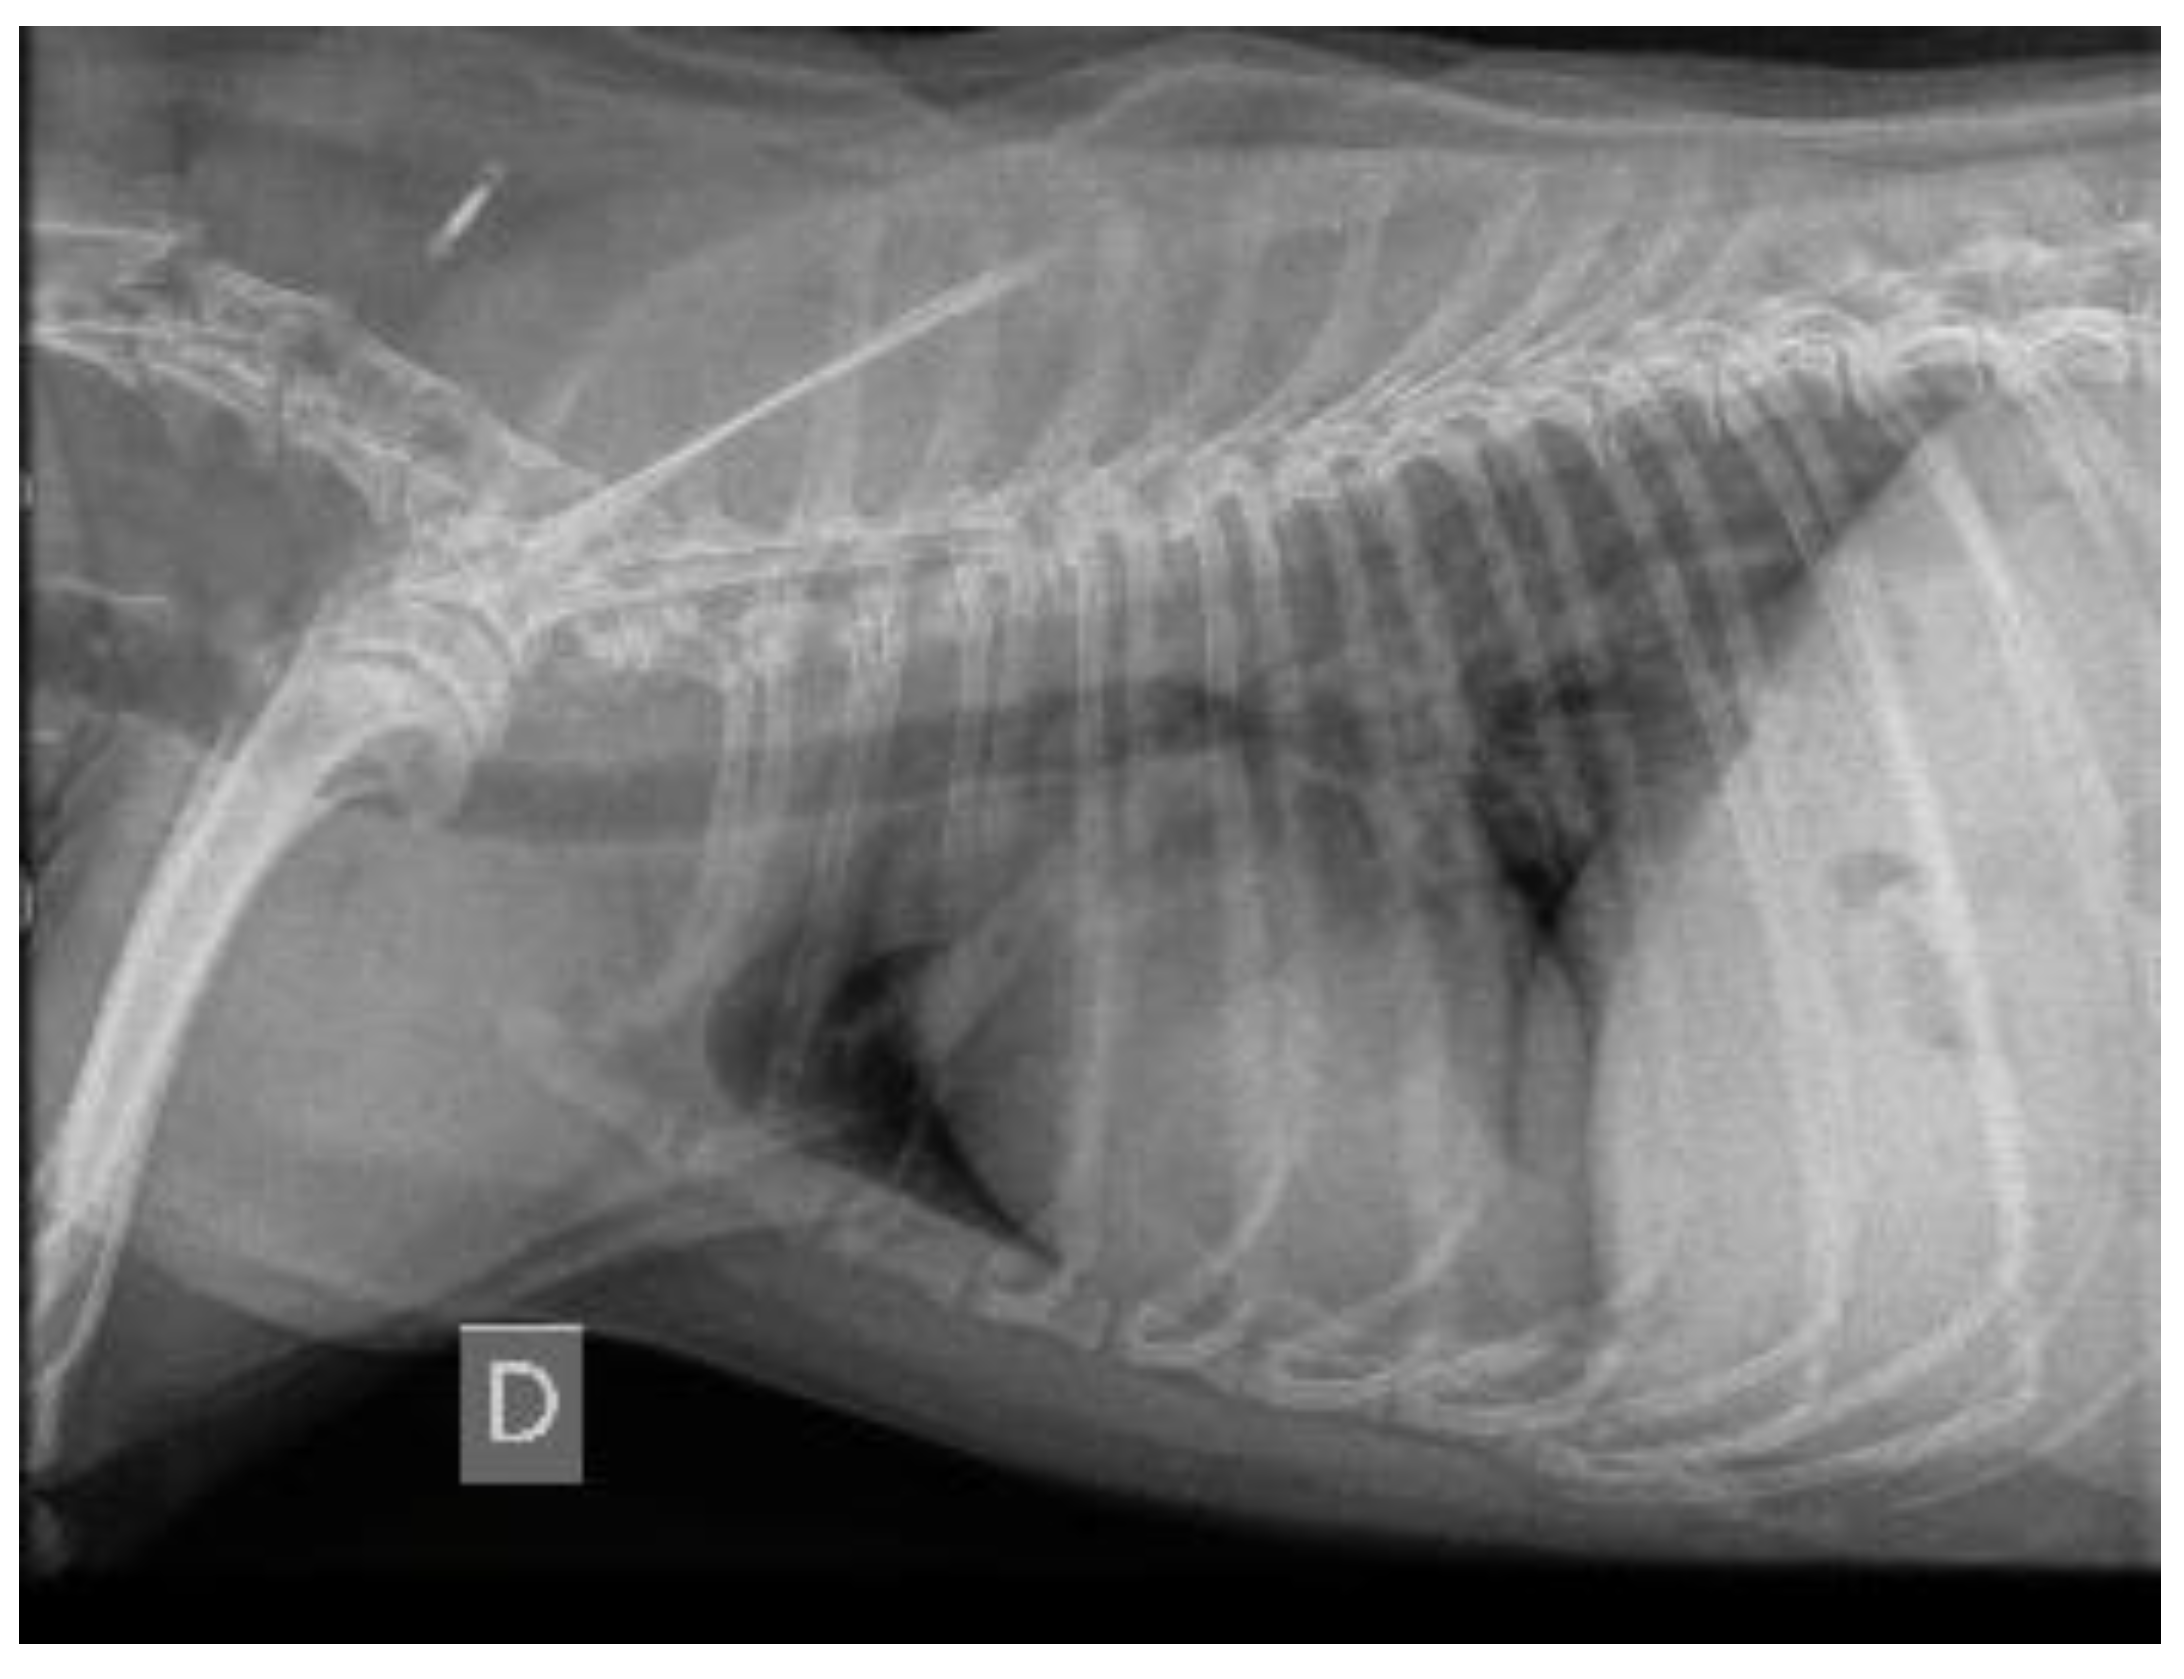

3.1.7. Thoracic Radiography Findings

3.2.1. Thoracic Radiography Versus Endoscopy